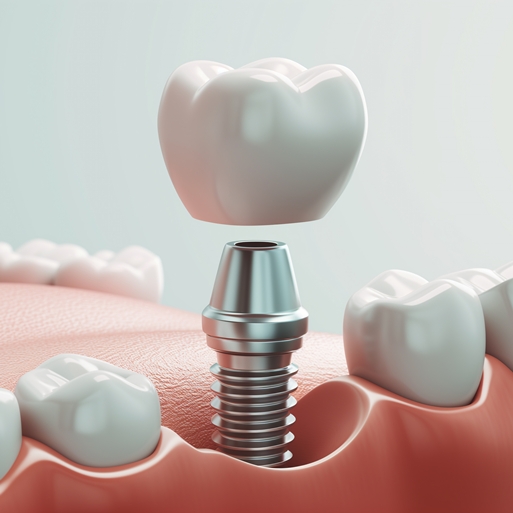

원데이 임플란트

발치,

임플란트 식립, 예비치아까지 단 하루만에

디지털로 빠르고, CAD/CAM 제작으로 튼튼한

예비치아, 통증 및 내원 횟수, 치료 기간을

획기적으로 줄일 수 있습니다.

전체 임플란트

일생에 한 번 뿐인 중요한 순간을 위해 풍부한

경험을 바탕으로 기술을 집약하였습니다.

전체 구강 기능과 조화를 고려해 자연치아와

최대한 비슷하게 재현합니다. -

더 완벽한 재도전

임플란트 재수술

기존 임플란트의 불편함을 정밀하게 분석하여

더 나은 결과를 위한 재시술을

신중히 설계합니다. -